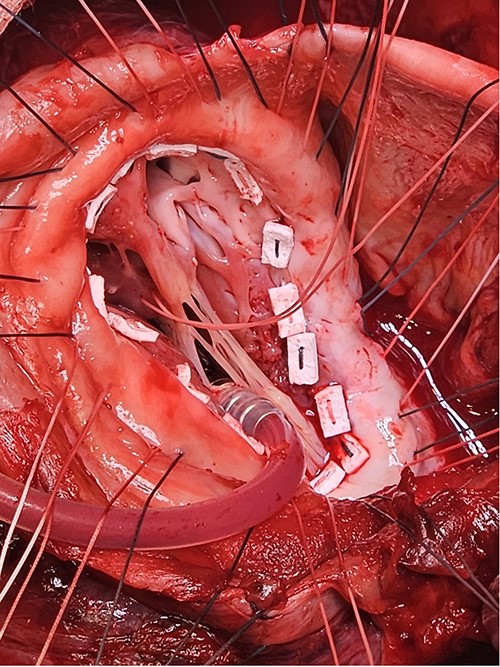

Following median sternotomy, cardiopulmonary bypass was instituted (bicaval drainage, ascending aortic return). Antegrade cardioplegia was delivered with aortic root venting and bicaval snaring. Dense adhesions surrounded the aneurysm, which had a thin wall, measured ⁓15 cm from LV apex to mitral annulus, and contained around 150 g of clot. The posterior mitral leaflet appeared retracted, preventing coaptation due to LV stretching. The aneurysm was resected (Fig. 2), and the LV wall repaired with a 5 × 3 cm patch, restoring normal LV size (Fig. 3). The musculotendinous junctions of the anterior and posterior papillary muscles were approximated using pledgeted 3–0 polypropylene sutures (Fig. 4). The patch repair was completed (Fig. 5), and the overlying sac oversewn for haemostasis.

The LV aneurysm was resected down to its neck into healthy ventricular scar tissue. The posterior chordae can be seen from the ventricular defect.

Pledgeted Ethibond sutures were placed circumferentially around the aneurysm mouth.